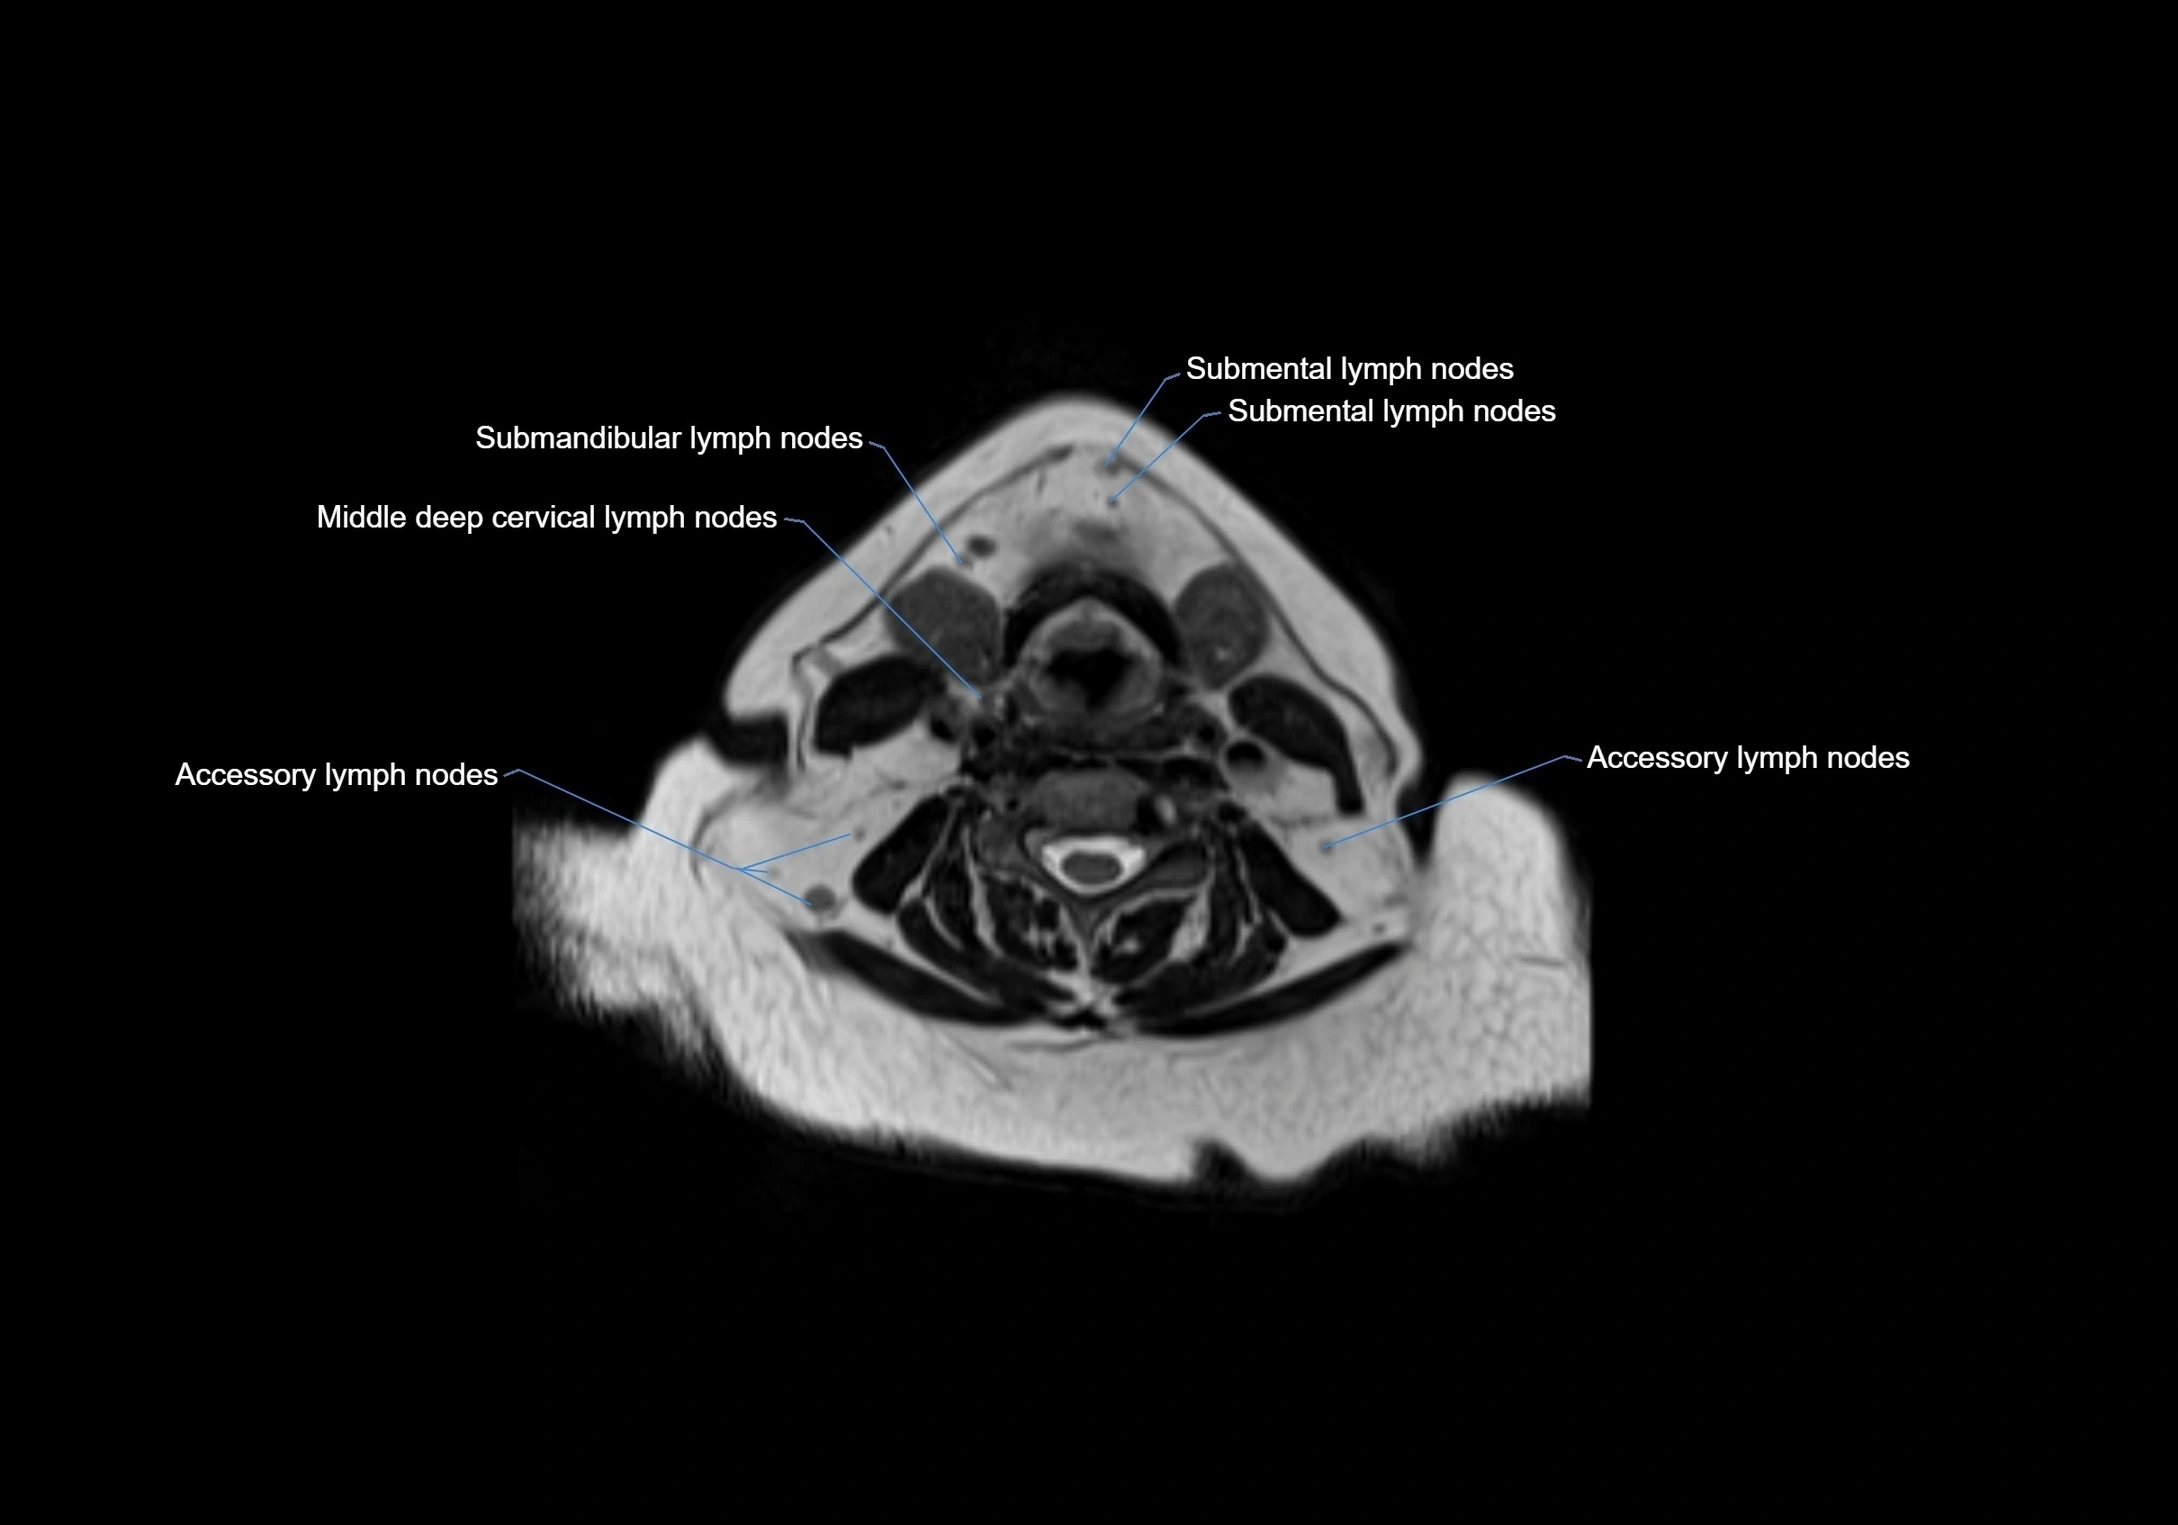

Accessory lymph nodes

Accessory lymph nodes are small, secondary lymph nodes located along the main facial and cervical lymphatic chains, often adjacent to primary lymph nodes, such as preauricular, submandibular, or occipital nodes. They are typically less than 5 mm in diameter, embedded within subcutaneous fat or connective tissue, and may be variable in number and location. These nodes provide additional filtration and immune surveillance for lymph collected from the face, scalp, and neck regions. Accessory lymph nodes are usually non-palpable in healthy individuals but may enlarge in response to infection, inflammation, or metastasis, making them clinically significant.

Location

• Found along primary lymph node chains, including preauricular, submandibular, parotid, and occipital regions

• Embedded in subcutaneous fat or superficial fascia, often lateral or posterior to primary nodes

• Variable in number; may occur unilaterally or bilaterally, depending on individual anatomy

MRI Appearance

T1-weighted images:

• Normal accessory nodes appear as small, oval hypointense to intermediate signal structures within subcutaneous fat

• Surrounded by hyperintense fat, enhancing contrast for visualization

• Pathological nodes may appear enlarged or rounded, sometimes with cortical thickening

MRI images

image